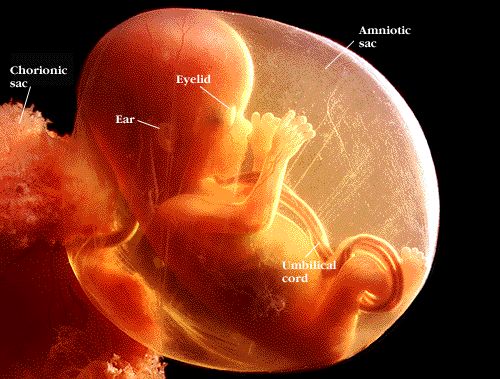

- Fóstrið er u.þ.b. 4,5 sm og vegur um 10 grömm en á næstu vikum vex það hratt. Æðum fylgjunnar fjölgar hratt og þær stækka til að geta séð fóstrinu fyrir allri þeirri næringu sem það þarf á að halda.

- Höfuðið er orðið hnöttóttara og er hlutfallslega mjög stórt miðað við búkinn

- Augnlokin eru orðin auðséð.

- Nú hafa mikilvæg líffæri fósturins myndast í aðalatriðum og þurfa nú aðeins að stækka og þroskast.

- Nýrun hafa tekið til starfa. Fóstrið kyngir legvatni og skilar því út sem þvagi.

- Nú er kviðarholið að verða nægilega stórt til að rúma meltingarveginn

- Heilinn og miðtaugakerfið halda áfram að þróast

- Litlar fingur- og táneglur taka að myndast.

- Í þessari viku myndast raddböndin.